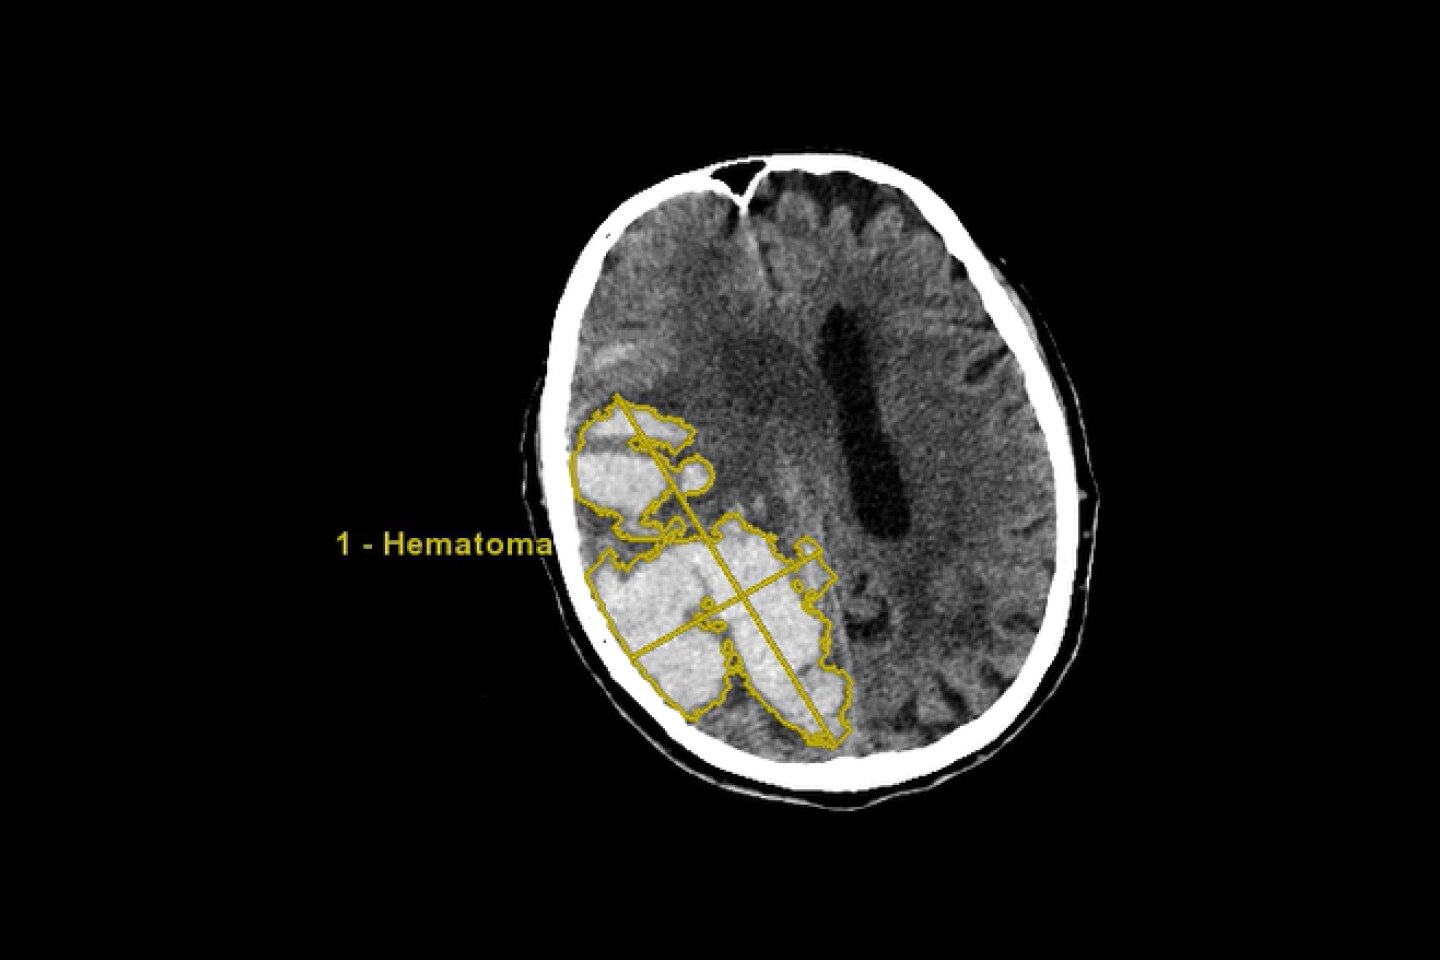

Adquisición de imágenes simplemente mejores

Más informaciónEstudios de casos